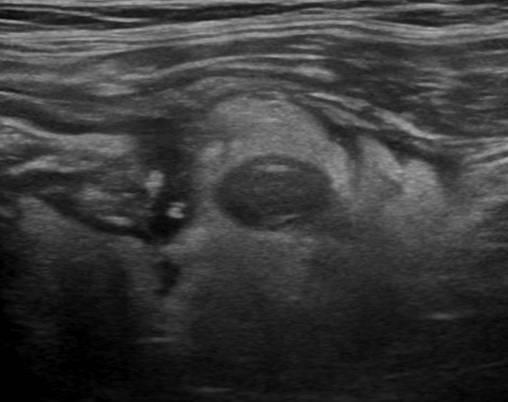

Viêm túi thừa

Viêm túi thừa - Ảnh 2

» Thông tin: Nam giới – 66 tuổi.

» Lâm sàng: Đau hố chậu trái / Sốt.